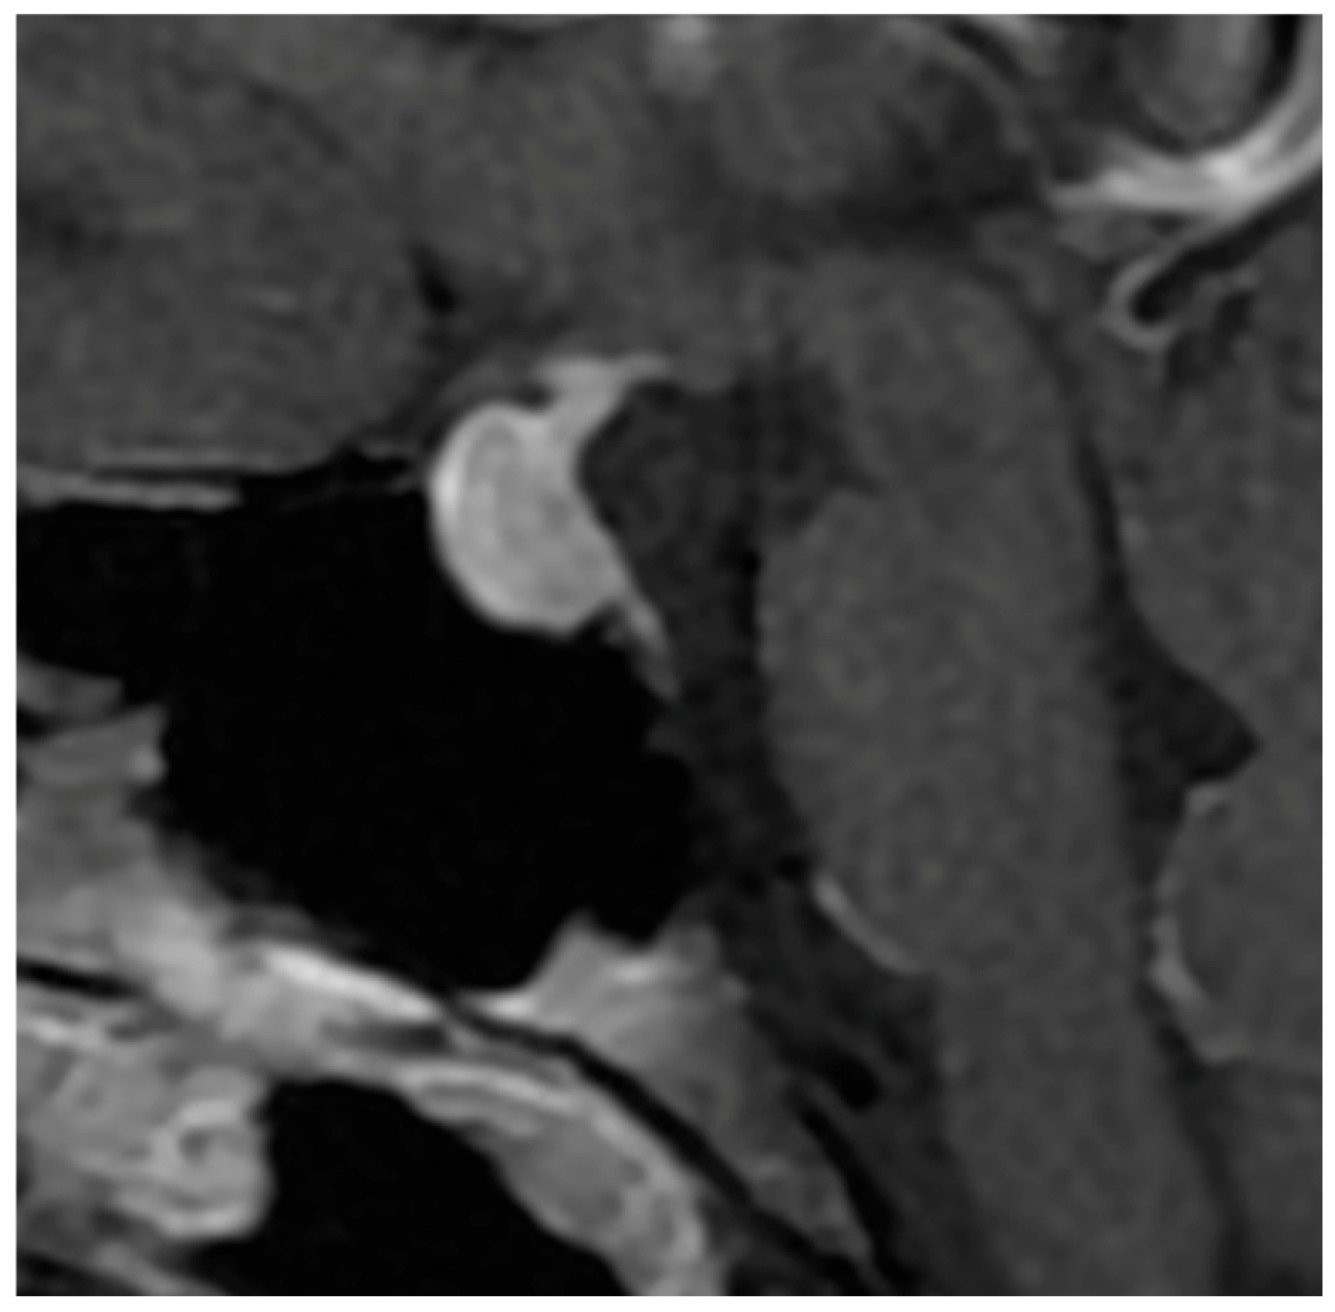

The pattern of enhancement after gadolinium injection provides an additional and highly informative contrast between both entities. Hypophysitis typically demonstrates an intense and homogeneous enhancement, reflecting diffuse vascularized inflammation, with reported rates of homogeneity ranging from 70% to 90% [37,73,74]. NFPMA characteristically show a heterogeneous and often delayed enhancement [75,76,77]. The use of early dynamic post-contrast sequences has been advocated by several authors, as it increases sensitivity for detecting subtle differences in enhancement kinetics between infiltrative and neoplastic processes (Figure 3) [78].

Figure 2. Sagittal T1-weighted image after Gadolinium injection showing a homogeneous enhancement of the pituitary mass in the case of hypophysitis.